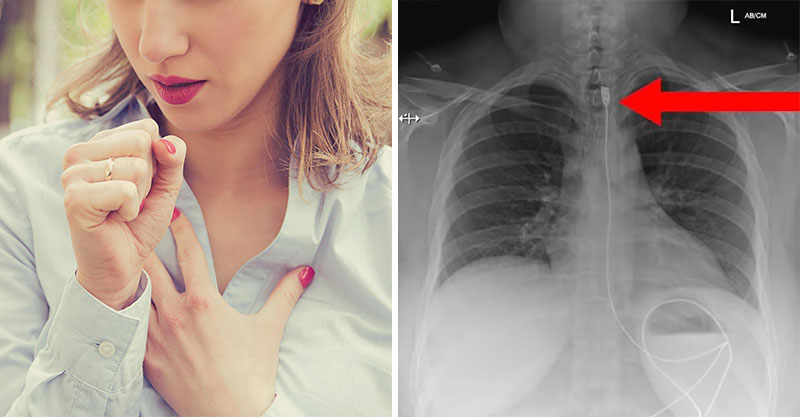

波蘭一名女子因為呼吸困難緊急送醫,照X檢查後,醫生竟然在她體內看到1公尺長的充電線......

根據外媒《Dailymail》的報導,波蘭醫療救援團隊「Gotowi Do Ratowania」收治了一起驚人病例,一名女子因為呼吸困難緊急送醫,她被安排照X光,檢查結果出爐後嚇壞醫生,因為她體內卡了一條長1公尺的iPhone充電線,從喉嚨處一路延伸到腸子裡。

女子這時才坦言,她因為患有「異食癖」,試圖吞下又細又長的充電線,不料充電接頭卡在喉嚨食道處,導致她無法呼吸,只好趕緊求助醫院。女子後來經過手術順利取出充電線,人已經康復出院。